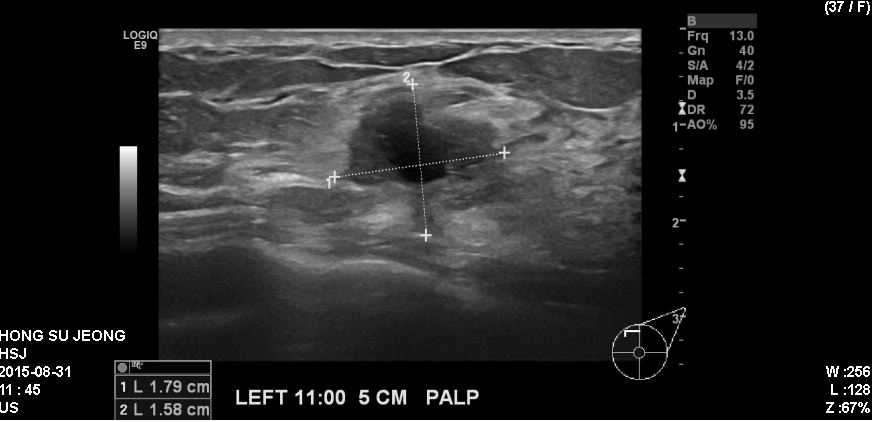

좌측 유방에 만저지는 몽우리로 내원하신 30대 여성분으로 본원에서 초음파 시행 후 좌측 11시 방향에서 5cm 떨어진거리에 있는 만져지는 혹 조직검사 시행하여 좌측 침윤성 유관암

진단 되었습니다.